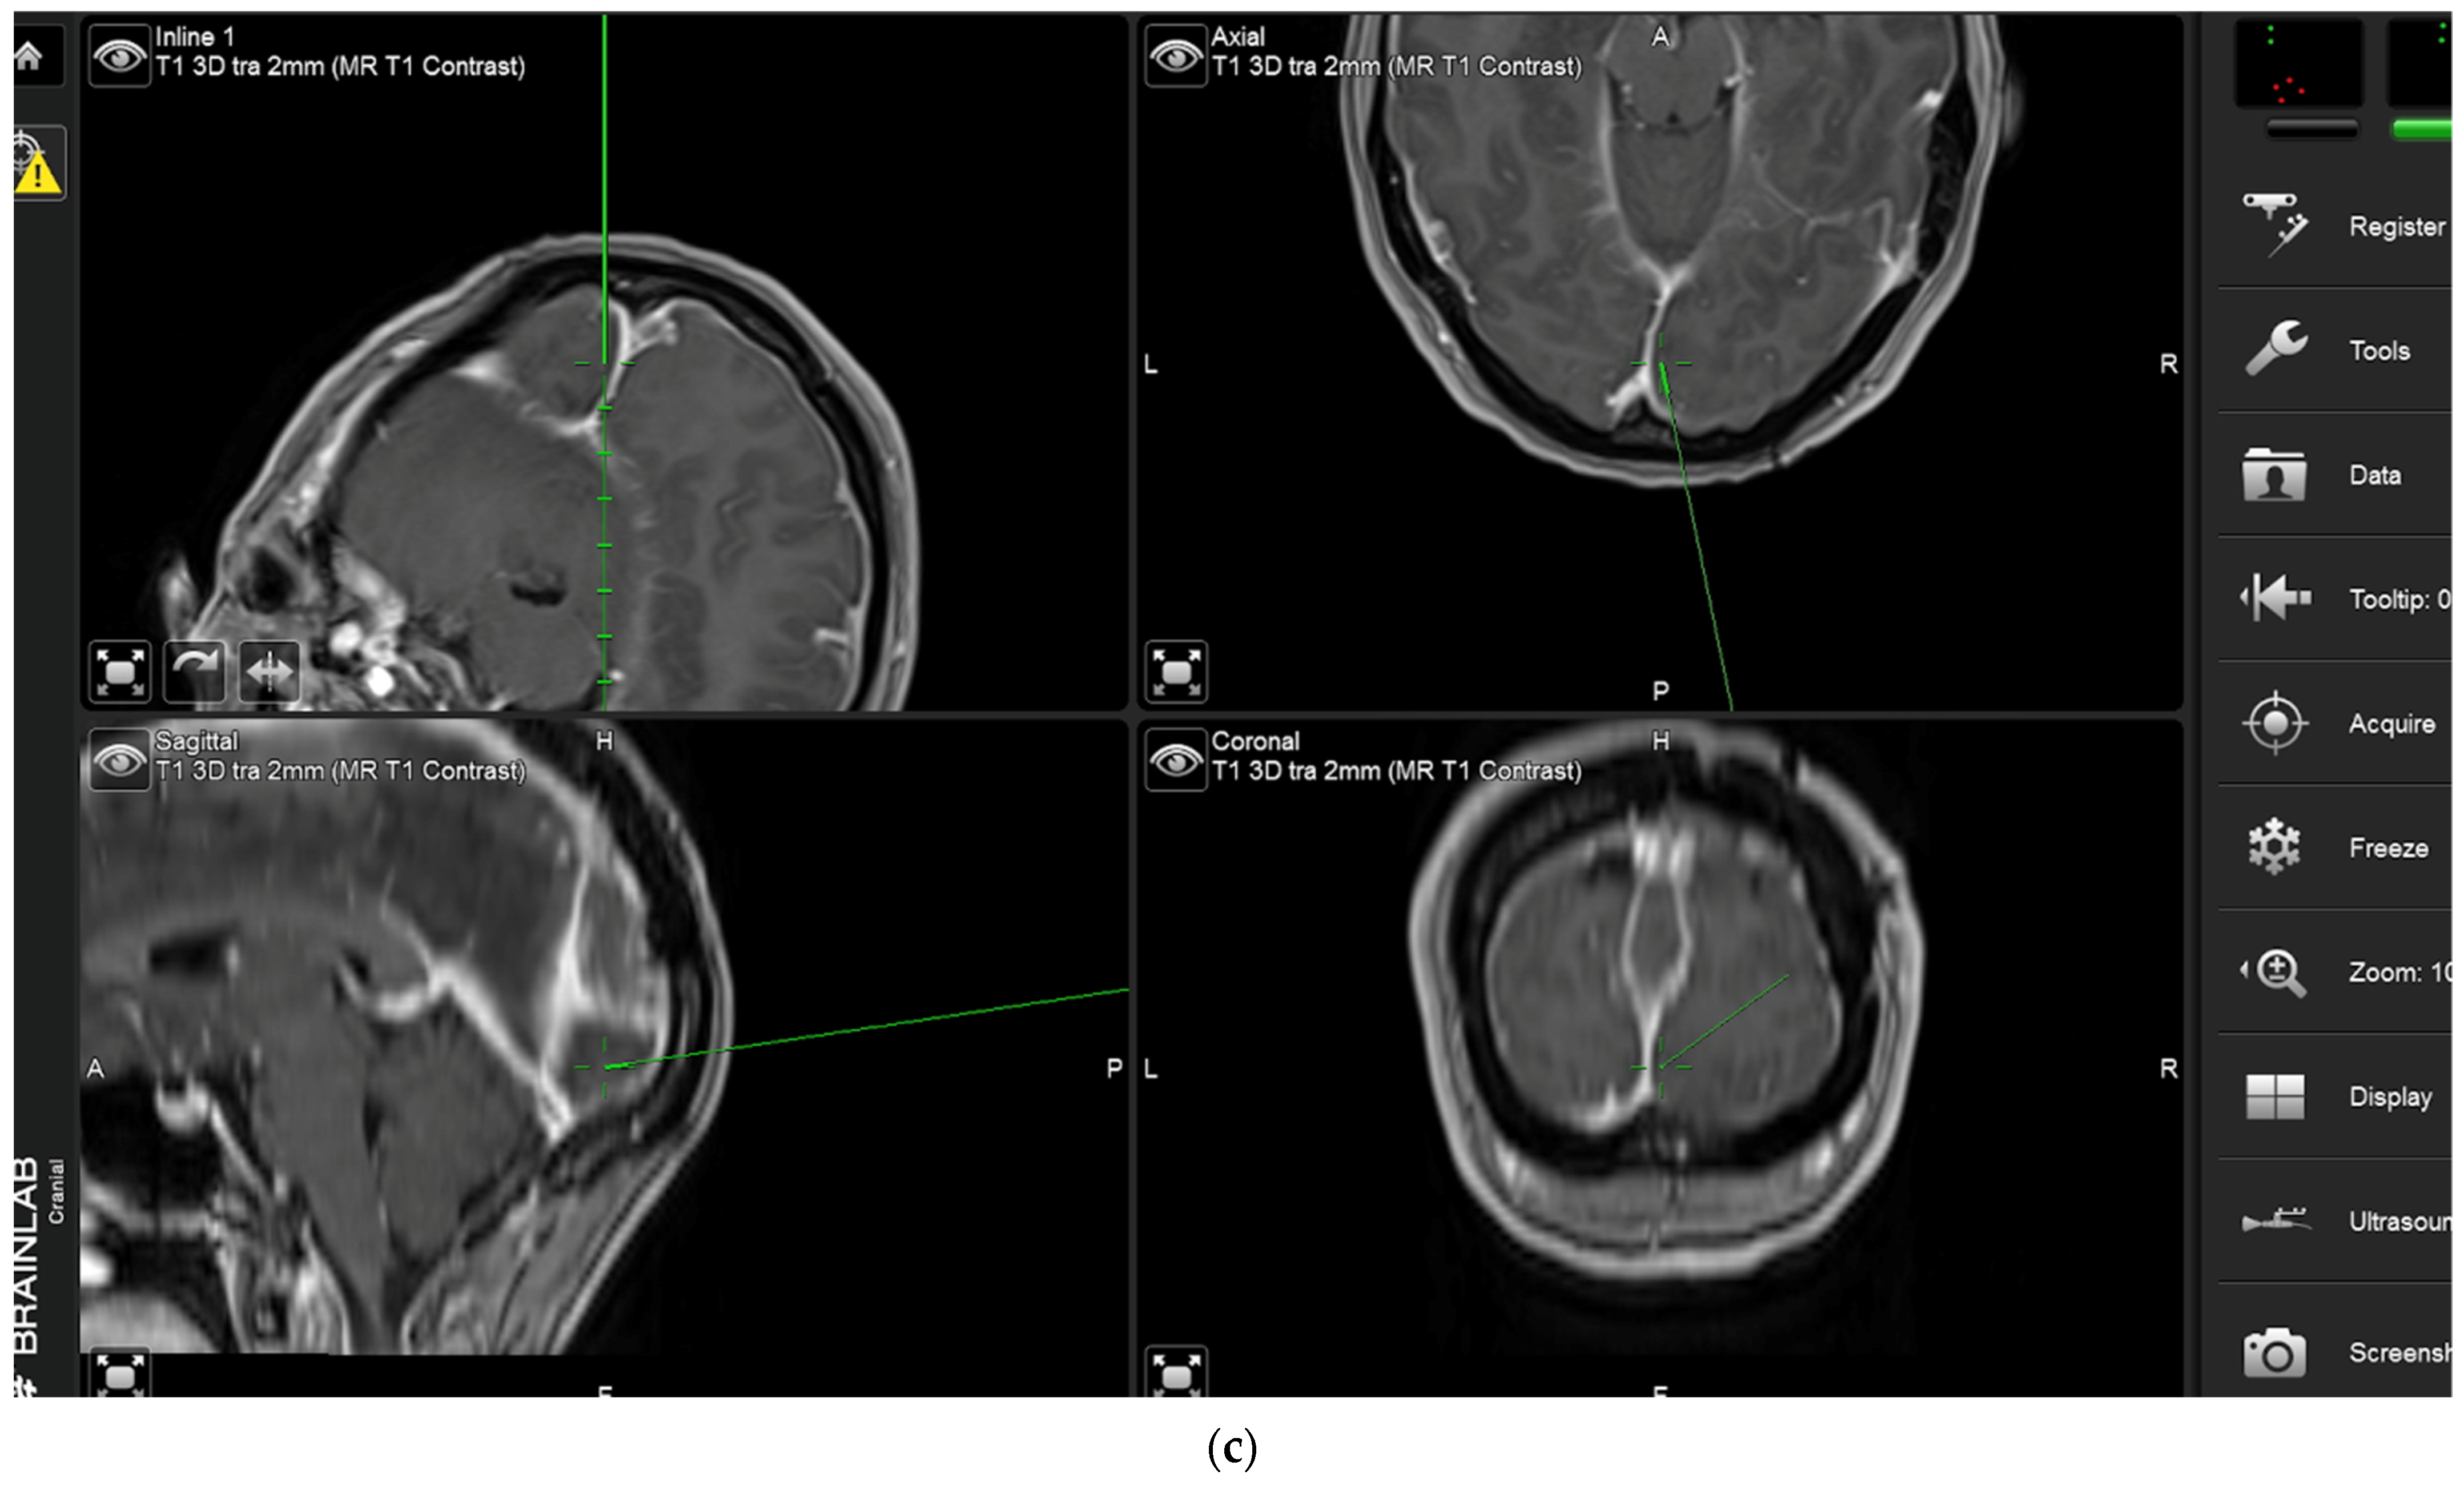

During the course of conventional white light surgery, the surgeon might encounter tissue which appears uncertain. From such “indeterminate” tissue the surgeon might require more information based on fluorescence. In such cases, the observation of fluorescence might lead to a change in surgical decision or surgical strategy. Such instances of indeterminate tissue may be found at the dural tail, in scar tissue with cases of recurrent meningioma, in the bone flap or at bony resection margins. In cases in which the surgeon requires more information based on fluorescence, the region in question is marked by the navigation pointer and a screenshot is taken. At this stage, the surgeon records his presumed diagnosis for the tissue area he or she desires more information for (“likely” or “unlikely” tumor) and his surgical decision based on his impression under white light (to resect or not to resect). The surgeon then switches to blue light, records whether he or she sees fluorescence, and states whether he or she plans to change surgical strategy based on fluorescence status. Under white light, the uncertain tissue is then biopsied for later histological evaluation. The entire process is recorded using the microscope’s video camera for later assessment by the review panel (Figure 2).

Biopsy from “indeterminate” tissue: In this study the surgeon might encounter tissue which appears uncertain (tumor or not, “indeterminate” tissue) during surgery and where fluorescence might be helpful. The location of a respective region is documented by the neuronavigation screenshot. The illumination is changed to blue light to determine whether the tissue fluoresces and a biopsy is then taken. The tissue interrogation procedure is recorded by video. (a) In this example a portion of the sagittal sinus infiltrated by meningioma has been resected. The anterior resection margin appears inconclusive as to whether it still contains tumor and is therefore regarded as being indeterminate. The location is documented using neuronavigation. The insert shows the pointer tip location marking the intended biopsy location. (b) No fluorescence is observed. The location is then biopsied. (c) Neuronavigation screenshot “A”: anterior; “P”: posterior; “L”: left; “R”: right).